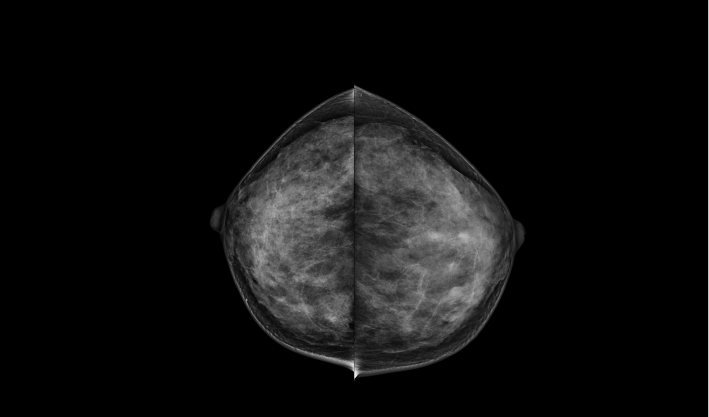

头尾位(CC位) 内外斜位(MLO位) 补充体位(根据需求)

致力于致密乳腺的早期癌变筛查和微钙化簇精准定性。